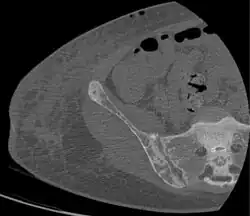

Brown tumors in the pelvis and a hip fracture.[18] -